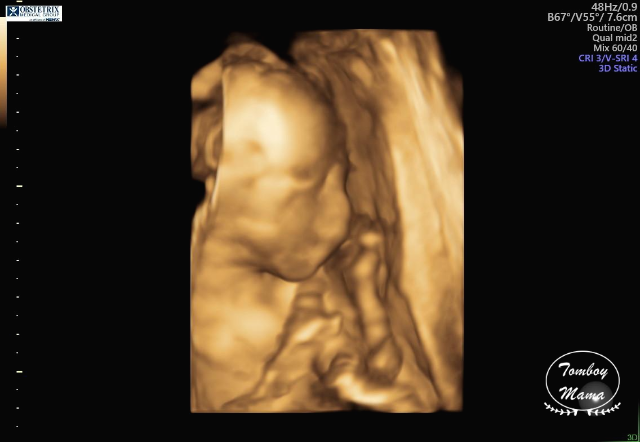

그리고 3D로 만나본 튼튼이. 사진들이 살짝 무섭긴 한데, 나중에 태어난 후의 모습이랑 비교하면 많이 비슷하려나 궁금하다. (찾아보니 입체 초음파 사진으로 생후 모습을 분석해 보여주는 한국 스타트업의 [베이비페이스]라는 프로그램이 있더라고요! 해보고 싶었는데, 25주 이상의 입체 초음파 사진이 필요하다고 해서 전 포기했어요... 저처럼 궁금하신 분들 참고하세요~)

(2) 단, 태아의 뇌에 낭종(choroid plexus cyst)이 있는데, 주로 다운증후군과 연관이 있는 증상이라고 했다. 자연스럽게 사라질 수도 있는 거고, 아이큐에 영향을 준다던가 하는 그런 문제가 아니기 때문에, 이게 발견되었다고 나중에 따로 추적하지는 않는다고 했다. 다만 다운증후군 가능성이 염려되면 (바늘로 찔러서 하는) 양수 검사를 할 수 있는데, 솔직히 지금 나에게는 추천하지 않는다며 3가지 이유를 얘기했다.